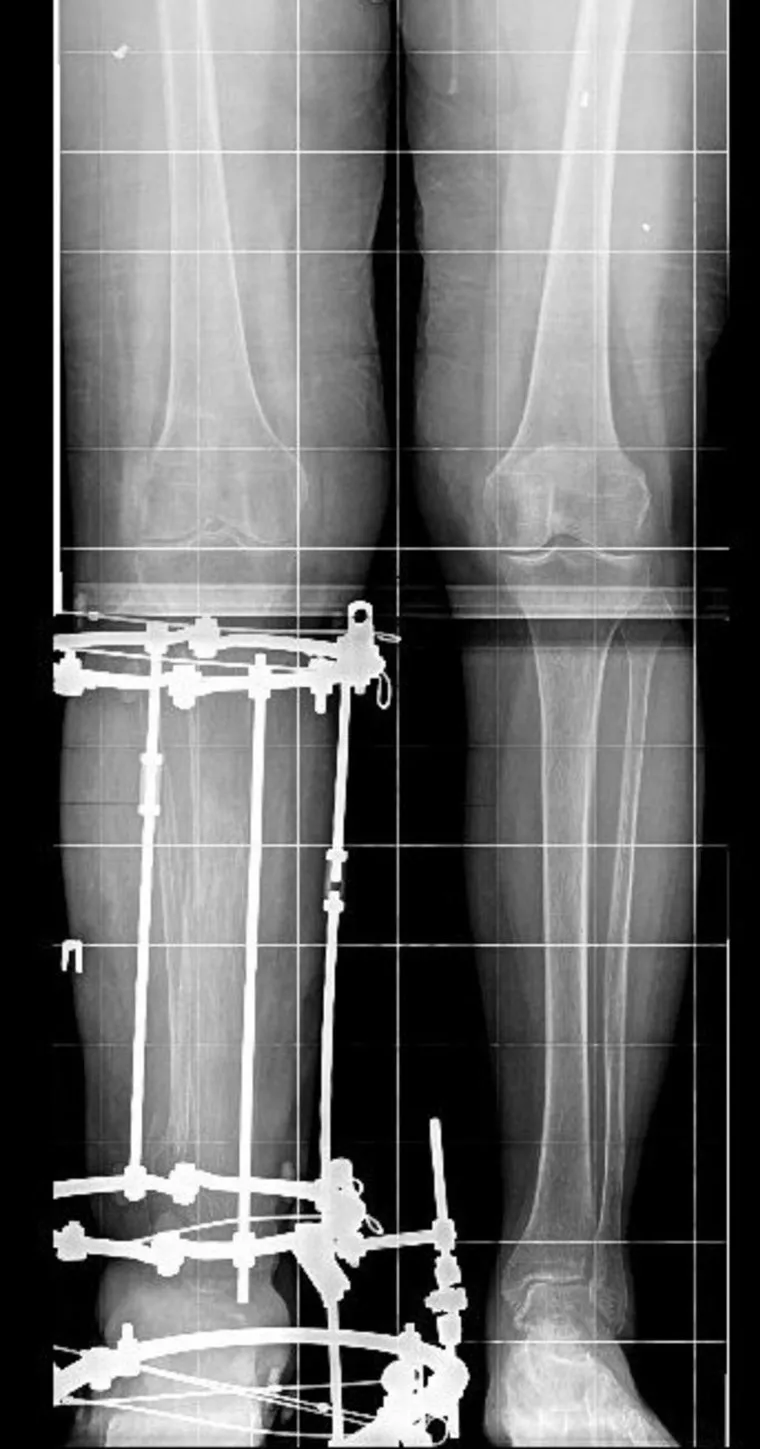

Курганский аппарат Илизарова спас от ампутации ногу жительницы Артемовска (Донецкая Народная Республика) Марины Лапенко, серьезно пострадавшей при артиллерийском обстреле. Она получила ранение в ногу, из-за которого ее стопа висела лишь на одном сухожилии. Ей подключили аппарат и спасли ногу. Затем женщину лечили врачи Центра Илизарова. Об этом сообщает пресс-служба медучреждения в своем tg-канале.

Основные повреждения пришлись на правую голень — были зафиксированы обширные дефекты костной и мягких тканей, а также выраженный остеопороз. После хирургического вмешательства пациентка смогла начать наступать на ногу и самостоятельно ходить. Медики отмечают, что сейчас для дальнейшей реконструкции потребуется восстановление плотности костной ткани с помощью активной реабилитации.

До поступления в российский центр Марина Лапенко перенесла десять операций, однако угроза ампутации сохранялась. В настоящее время специалисты продолжают наблюдение за пациенткой и отмечают положительную динамику: устойчивость ноги восстановлена, а опорная функция конечности улучшилась.